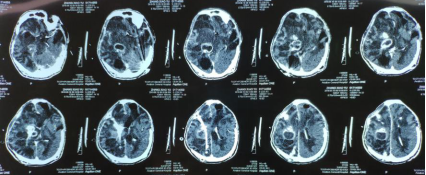

近日,傅继弟教授颅内感染团队(以下称该团队),接诊了一名外省转来的危重颅内感染患者。该患者男性,27岁,3年前因脑外伤后继发性脑积水,行双侧侧脑室分流手术,随后继发颅内感染,反复发热长达3年,颅内出现多达6个脓肿!

患者被120送至该团队时已经昏迷并出现脑疝,呼吸循环开始衰竭。此时他脑内有2根分流管,且与6个脑脓肿粘连,此类手术风险极高!此分流合并颅内感染病例,目前国内外也少见报道。6个脓肿如何处理?2根粘连的分流管如何取出?患者能否度过危险期?能否清醒?

面对这些巨大的压力和挑战,该团队经过快速讨论后,随即制定了详细的手术方案。经过7个小时的显微手术,6个脑脓肿、2根严重粘连的分流管均被取出!

由于运用显微手术技术,术中完整剥离了脓肿壁,最大限度保护脑组织,大大减少病变周围脑组织损伤,患者在术后3天便恢复了意识!